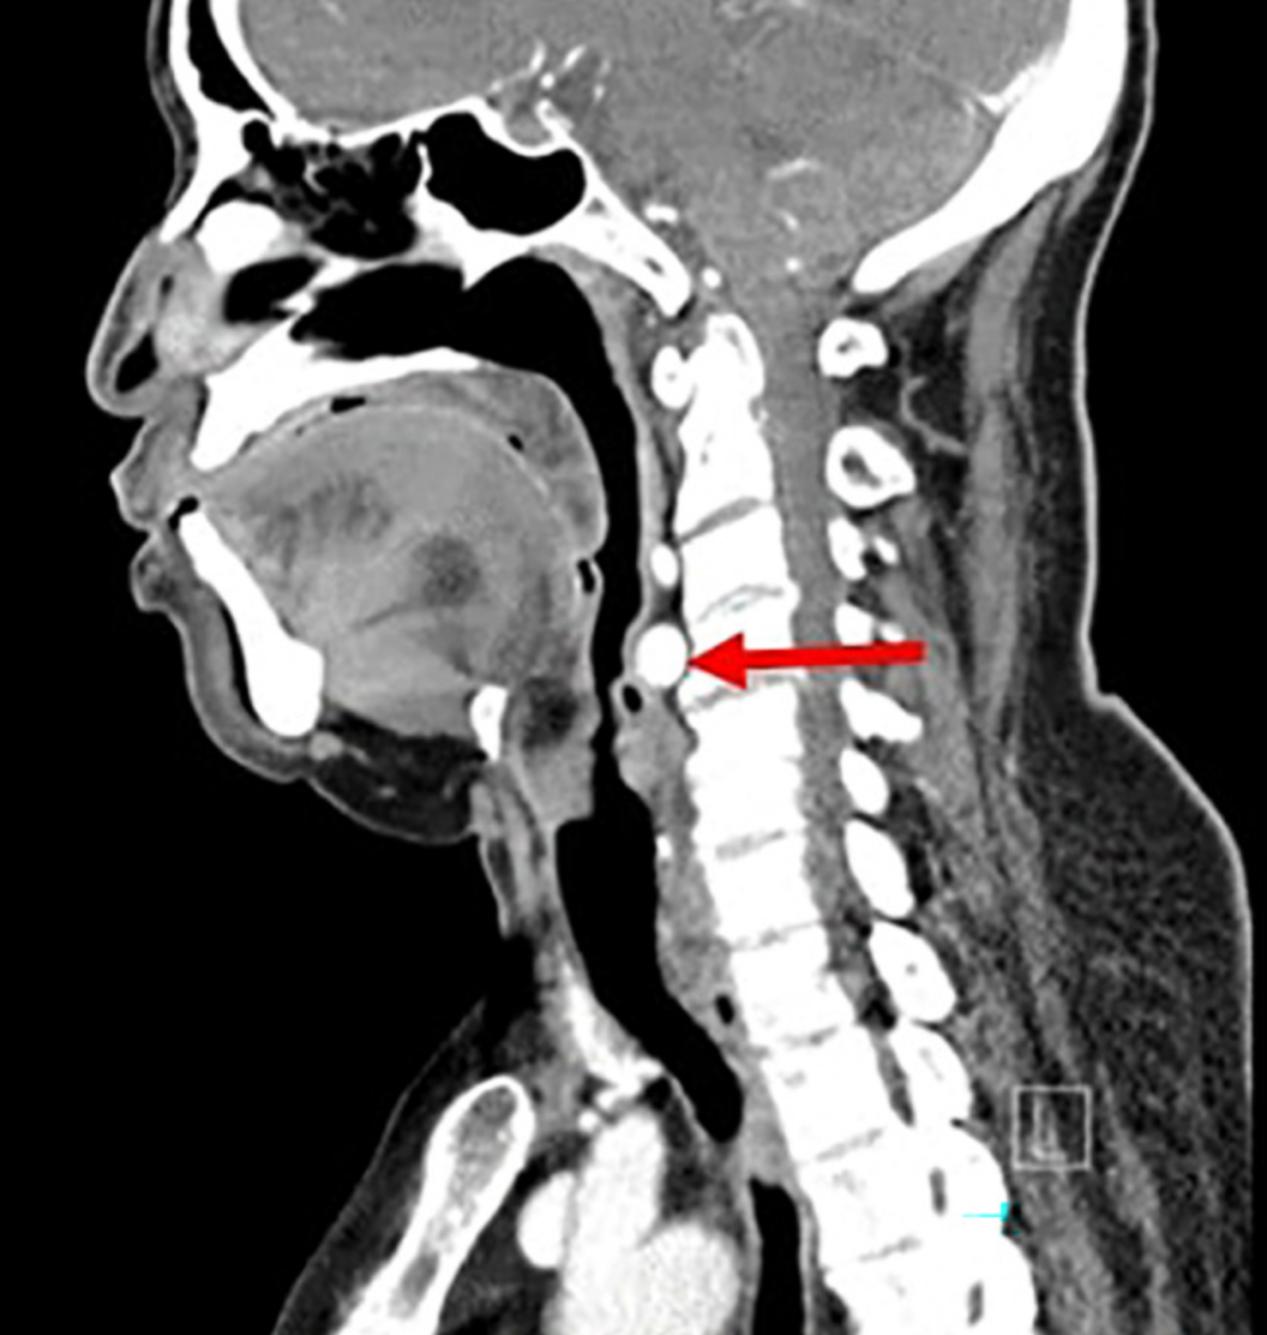

一名72岁的患者因轻微的慢性进行性发音困难就诊,患者诉嗓音的波动影响了他作为教堂歌手的活动。他无吸烟史,否认吞咽困难或咳嗽等其他相关症状。纤维频闪喉镜检查显示一个搏动性环后肿块压迫右侧杓状软骨(图1)。考虑到肿块的搏动性外观,怀疑是颈内动脉的解剖变异。耳鼻喉科余检查均正常。

图1 喉镜检查。咽后壁肿物(红色箭头),压迫右侧杓状软骨(白色箭头),右声带(绿色箭头)无损伤